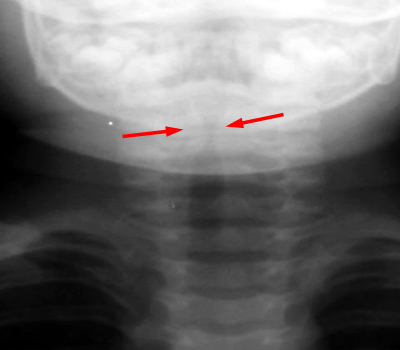

A lateral soft tissue radiograph will show the AP narrowing of the subglottic trachea, which normally should maintain the same AP diameter to the thoracic inlet. An AP soft tissue neck film will also show subglottic narrowing, but this can be confused with normal respiration changes. CXR will usually show signs of the viral bronchitis. Most importantly, the radiographic examination will also determine if there is a retropharyngeal abscess or an airway foreign body.

AP and lateral soft tissue exam of the neck demonstrates the subglottic edema.

Note that the epiglottis is not thickened as in epiglottitis.